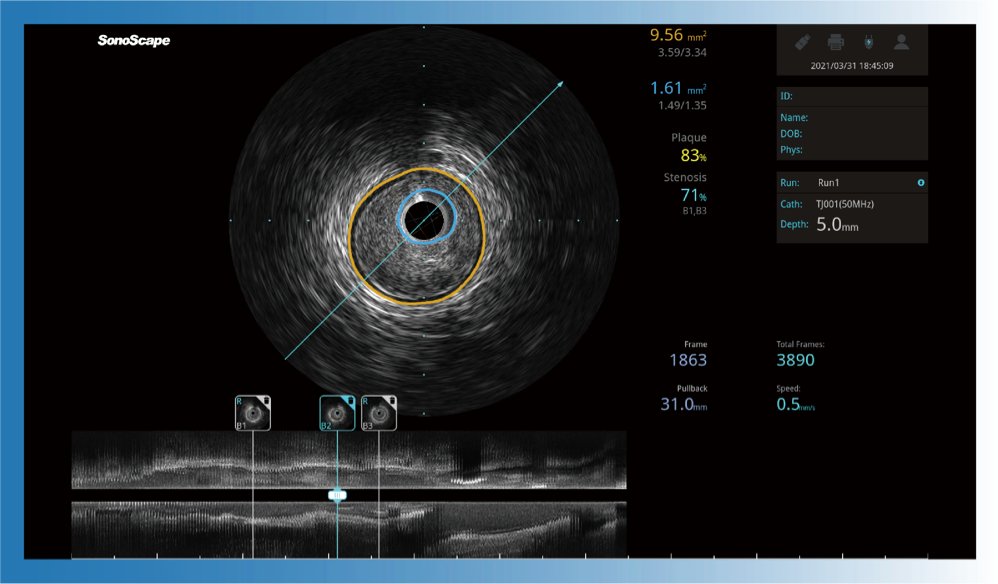

对比传统IVUS导管成像,银河优越会宽频IVUS图像的近场支架梁显影更细腻,远场中膜外血管仍清晰可辨,兼顾远中近,兼顾分辨力与穿透深度

一键智能描迹,自动测量斑块负荷、面积狭窄率等指标,准确率高于90%